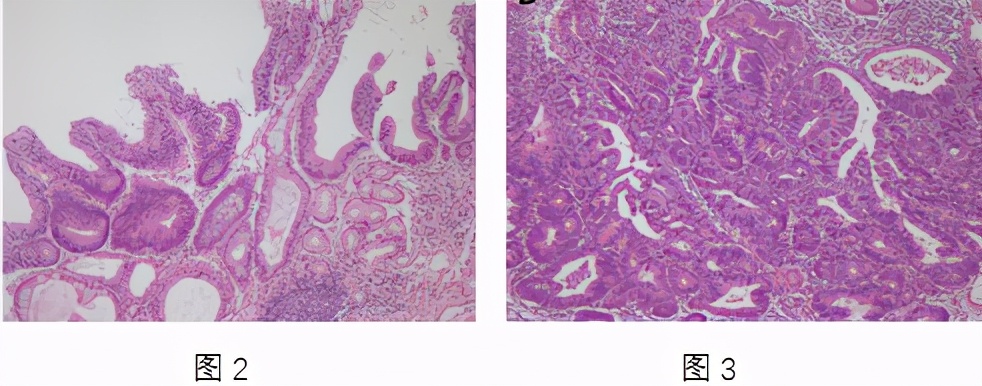

图2为内镜活检标本诊断为低度不典型增生,图3为内镜黏膜下剥离术切除标本诊断为高分化胃腺癌。表明活检对低级别上皮内瘤变的诊断在内镜黏膜下剥离术切除后被诊断为高分化胃腺癌。